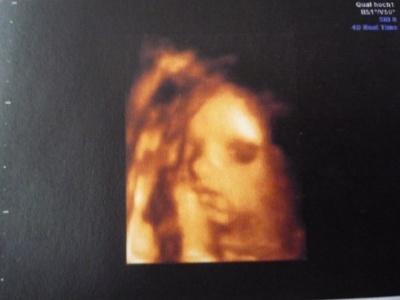

Huhu ich bin wieder da. Also die Maus ist Mopsfidel. Es war schön sie kurz zu sehen. Die kleine ist knapp 35cm gross und hat 700g, laut FA völlig im Rahmen. Der Doppler war auch perfekt, der hätte wohl nicht besser laufen können. Da die SS momentan so gut verläuft, traute ich mich doch glatt mal zu fragen ob ich evtl. doch aussicht auf eine Spontane Geburt hab. Dies verneinte er allerdings. Er meinte das ich sicher keinen Finde der dieses Risiko auf sich nimmt. Na toll...ich habe doch soo gehofft. Nun ja dann werde ich mal in dem KH hier in der Nähe mal einen KS Termin ausmachen. Ich habe ihm gefragt was bei ihm der 3D kostet...ganze 111€ ich habe ihm dann erzählt das es hier extra ein Studio dafür gibt wo es nur 80€ kostet und die darauf spezialisiert sind. Er meinte beim 3. Screening in 4 Wochen werden wir mal verhandeln. Ich hoffe ja das er sich im Preis etwas drücken lässt. *hoff* Um zu zeigen das er ein gutes US Gerät hat, hat er doch glatt mal schnell auf 3D umgestellt. Komisch wie real das ganze auf einmal wird wenn man die Mäuse soo genau erkennt. Die Zeit rennt einfach. Wenn ich bedenke das ich dann so langsam den Termin für den KS ausmache. So in 4 Wochen, also am 29. darf ich die Maus dann wieder sehen. Ich hoffe die Zeit vergeht schnell. LG Antje

oh das sind schöne Bilder Ja der 3d ist echt extrem teuer, bei meiner kostet es 50 Euro, da sie aber bei dem anderen auch nur so kurz geschallt hat denk ich sind die 50 nicht gut bei ihr angelegt. Werde vielleicht bei meinem neuen machen jenachdem was es kostet

Das ist aber ein süßes 3 D Bild, ja bei mir will hier ein Arzt für 4 Fotos und eine CD 100 euro haben. ABER ich habe großes Glück und das KH wo ich hin will hat im September Tag der offenen Tür und da bin ich für einen 3D/4D Ultraschall angemeldet und das ganze kostenlos, nur die 20 euro für cd und bilder.....jaaa supppiii....die 80 euro die übrig bleiben lege ich dann lieber in was für die kleine an Lg